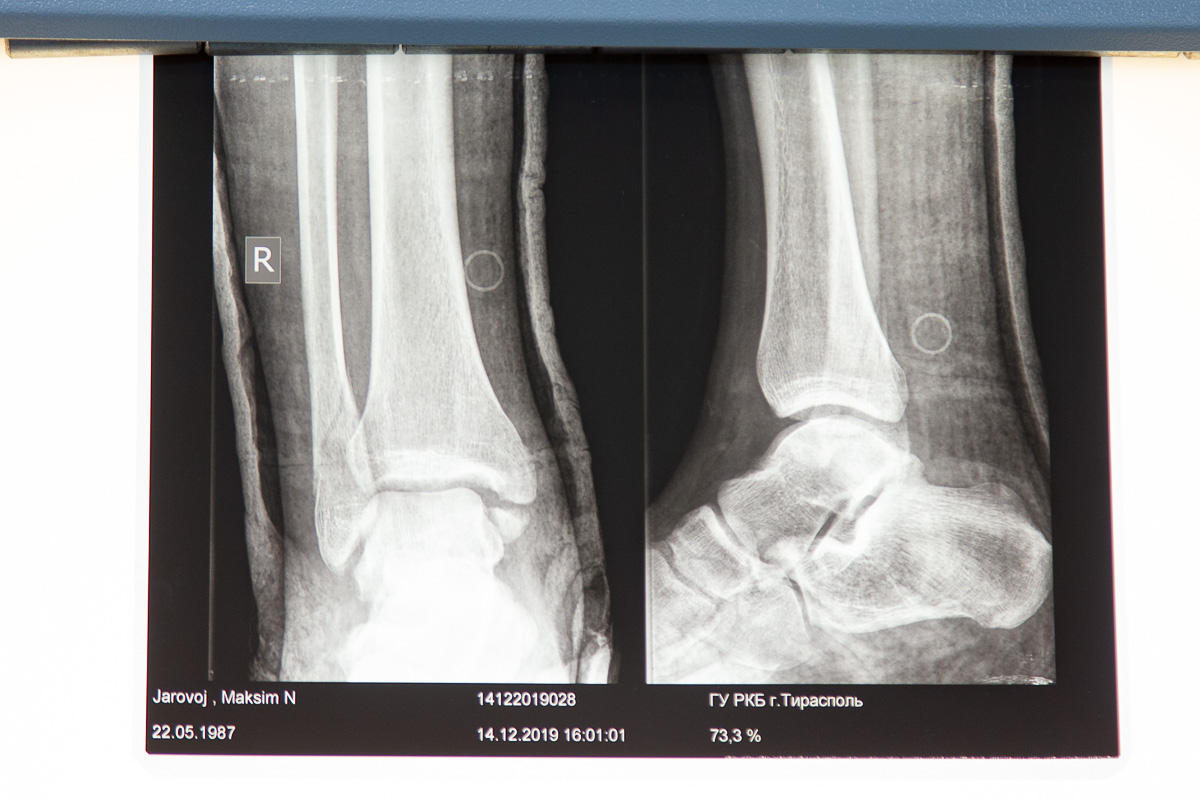

В кабинете, где проходит первичный осмотр, поставили негатоскоп: на светящемся экране врач может детально рассмотреть снимок из рентген-кабинета. Его уже не нужно распечатывать - доступна электронная версия.